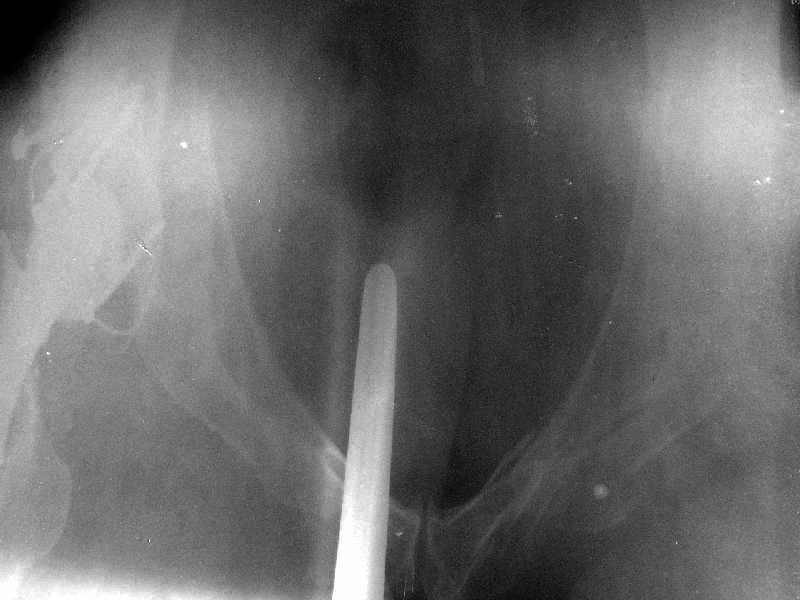

Обратились коллеги из городской больницы N36. Женщине 39 лет по поводу диспластического коксартроза около года назад выполнено эндопротезирование правого тазобедренного сустава. Вчера ехала на госпитализацию на протезирование второго сустава, и попала в аварию.

Получила поперечный перелом правой вертлужной впадины (снимок прилагается) с переломом ветвей лонной кости на другой стороне (inletview также в приложении), а также поперечный перелом дистального метафиза бедра на этой же стороне. Что посоветуете в отношении протеза и впадины? Спасибо заранее.

A colleague of mine from another hospital requests opinion. A female 39 years old was operated ~1 year ago - right side THA for hypoplastic hip. Yesterday she was going to the hospital for THA ofthe second hip but got involved in a car accident.She admitted with right acetabular and left rami fractures (images attached). Also trasverse fracture of the right distal femur.Seeking your advice regarding the acetabular fracture. THX!